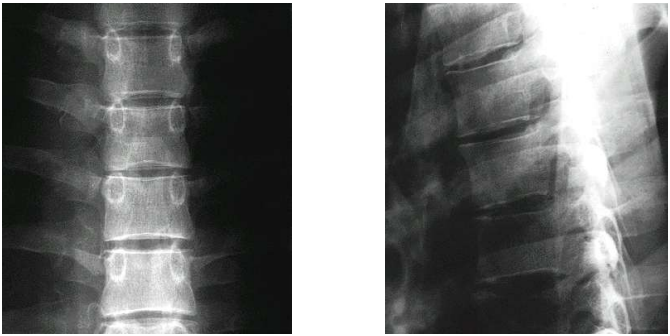

Brustwirbelsäule - Lendenwirbelsäule

Brustwirbel

filigranere Wirbelkörper

Dornfortsatz fällt steiler ab

Lendenwirbel

massiverer Wirbelkörper

Dornfortsatz ist massiver und breiter

andere Stellungen Gelenkflächen

Brustwirbelsäule

Lendenwirbelsäule